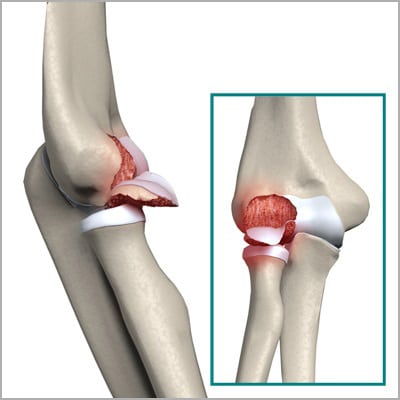

Перелом шейки и головки лучевой кости

При переломе руки в локтевом суставе человеком утрачивается способность вращения лучевой кости. Это приводит снижению функциональной активности предплечья. Пострадавший также не может повернуть кисть, взять любой предмет. Иногда костные отломки смещаются в суставные полости, блокируя движения. Опасным осложнением травмы становится повреждение костными фрагментами кровеносных сосудов, ответственных за трофику лучевой кости. При незначительном смещении фрагментов операция не проводится. Функции локтя восстанавливаются при наложении гипсовой повязки. Если фрагменты блокировали сочленение, то производится внутренняя их фиксация винтами и пластинами. При многооскольчатом переломе пациенту показано эндопротезирование костной головки.